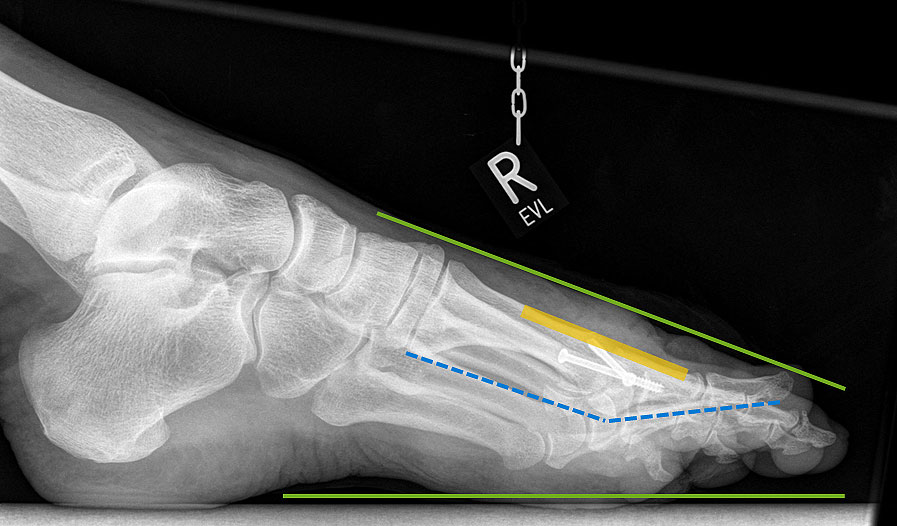

Alternativ kann bei einem elevierten Metatarsale I auch eine sagitale Korrektur der Fehlstellung durch eine Z-Osteotomie erreicht werden (Abbildung 22). Diese Osteotomie erlaubt eine Plantarisierung und ggf. auch Verlängerung des Metatarsale I.